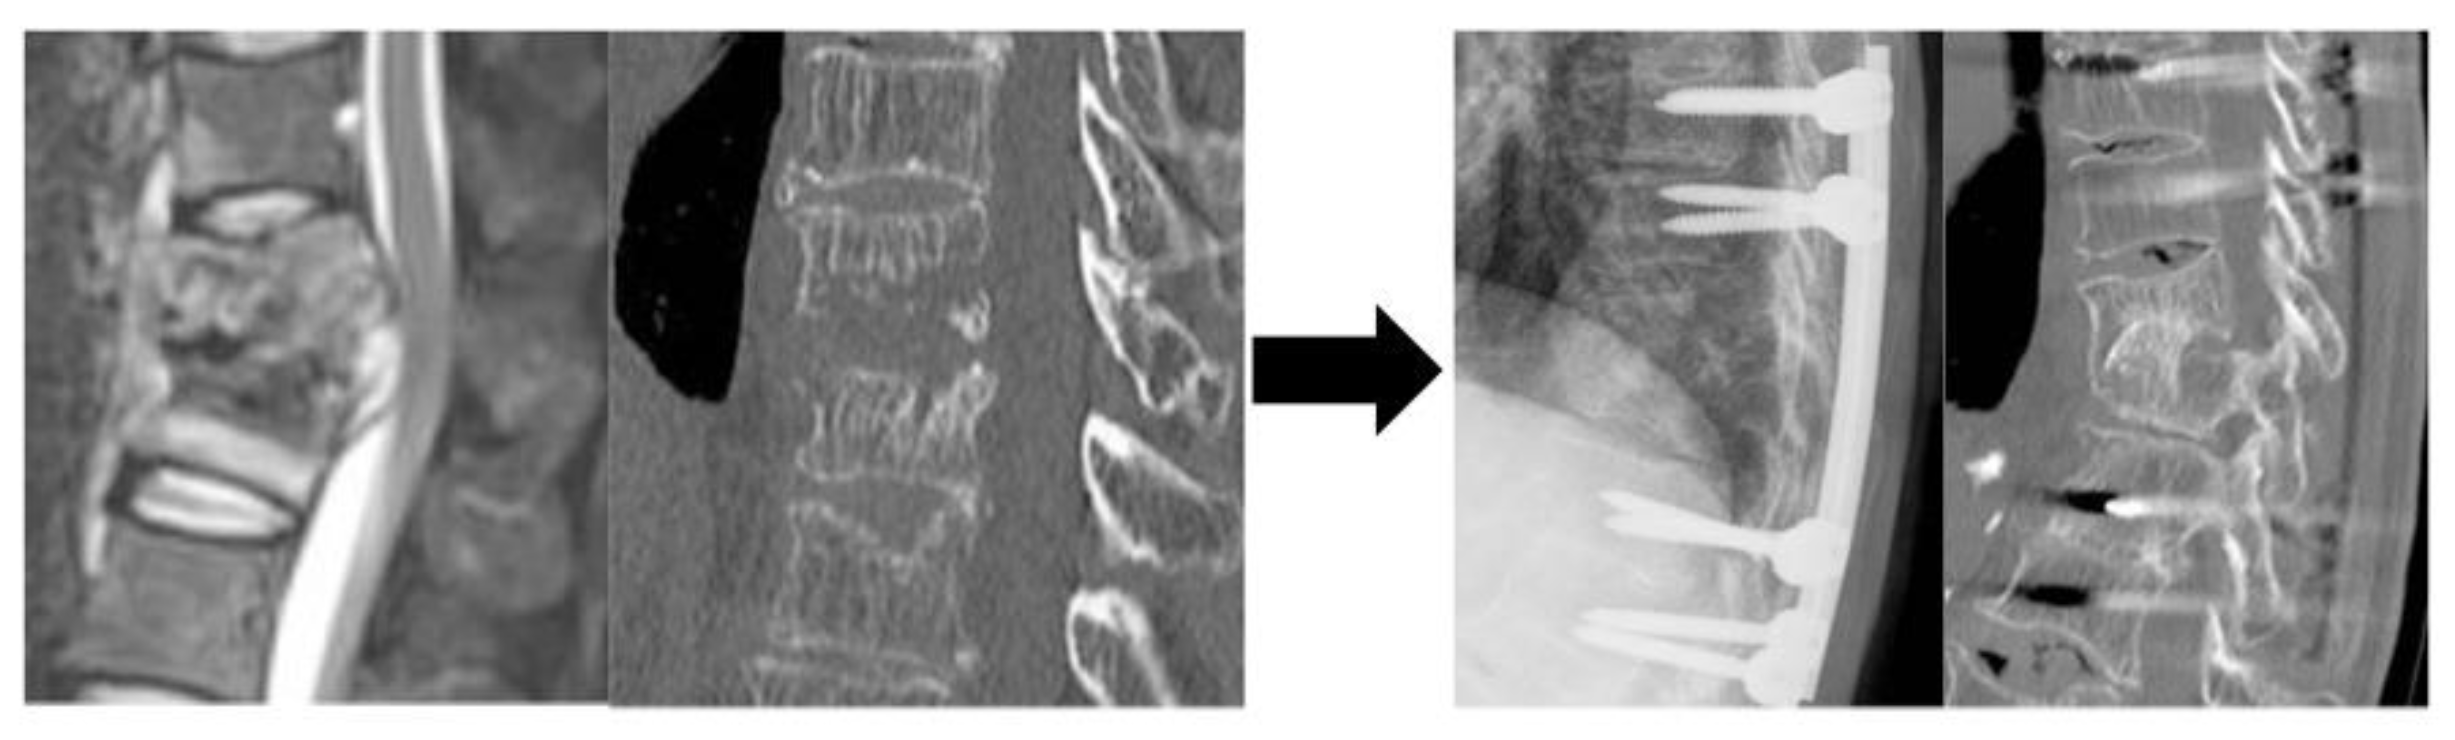

Figure 2.

A representative of Group B patients who underwent ASF alone but underwent revision surgery. A Preoperative CT: T12, L1 vertebrae with bone destruction B Immediate postoperative X-ray: fibula grafted C Preoperative CT: postoperative kyphosis angle has progressed due to bone graft dislocation D Postoperative CT: Posterior instrumentation was added, and bone fusing was achieved 6 months later. Abbreviation: CT, computed tomography; T, thoracic; L, lumbar.